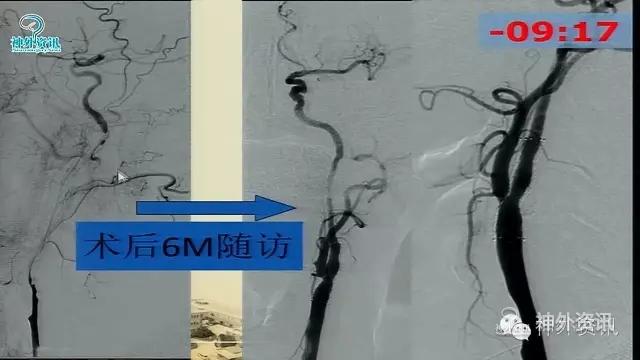

万杰清教授:慢性颈动脉闭塞再通技术及临床效果